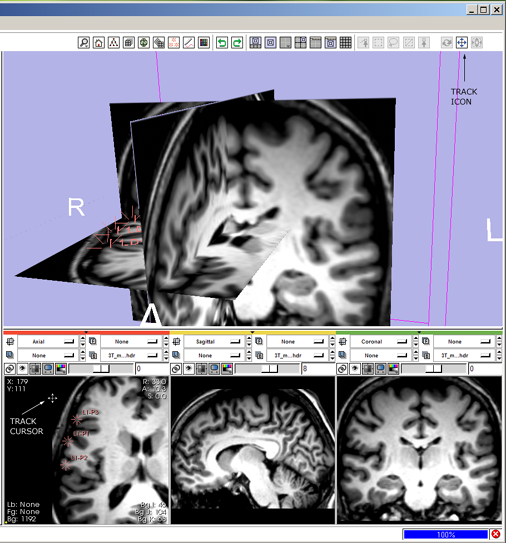

| + | 3(novice) '''track:''' click the view track mouse-mode icon [[image:ToolbarMousePan.png]] | ||

* --> mouse-track icon highlights and all others deselect, cursor changes to indicate mouse-track mode. | * --> mouse-track icon highlights and all others deselect, cursor changes to indicate mouse-track mode. | ||

* then left-Click and drag in the 3D Viewer to translate the view left-right, and up-down, | * then left-Click and drag in the 3D Viewer to translate the view left-right, and up-down, | ||

| − | 3 ''' | + | 3(expert) '''track:''' alt+left-Click and drag in the 3D Viewer, |

| − | + | * --> mouse-track icon [[image:ToolbarMousePan.png]] highlights and all others deselect; cursor changes to indicate mouse-track mode; view tracks. | |

| − | 4 '''place fiducials:''' click the mouse-place icon [[image:ToolbarMousePlace.png]] | + | [[image:SB3.png]] |

3(novice) track: click the view track mouse-mode icon ![]()

- --> mouse-track icon highlights and all others deselect, cursor changes to indicate mouse-track mode.

- then left-Click and drag in the 3D Viewer to translate the view left-right, and up-down,

3(expert) track: alt+left-Click and drag in the 3D Viewer,

- --> mouse-track icon

highlights and all others deselect; cursor changes to indicate mouse-track mode; view tracks.

highlights and all others deselect; cursor changes to indicate mouse-track mode; view tracks.